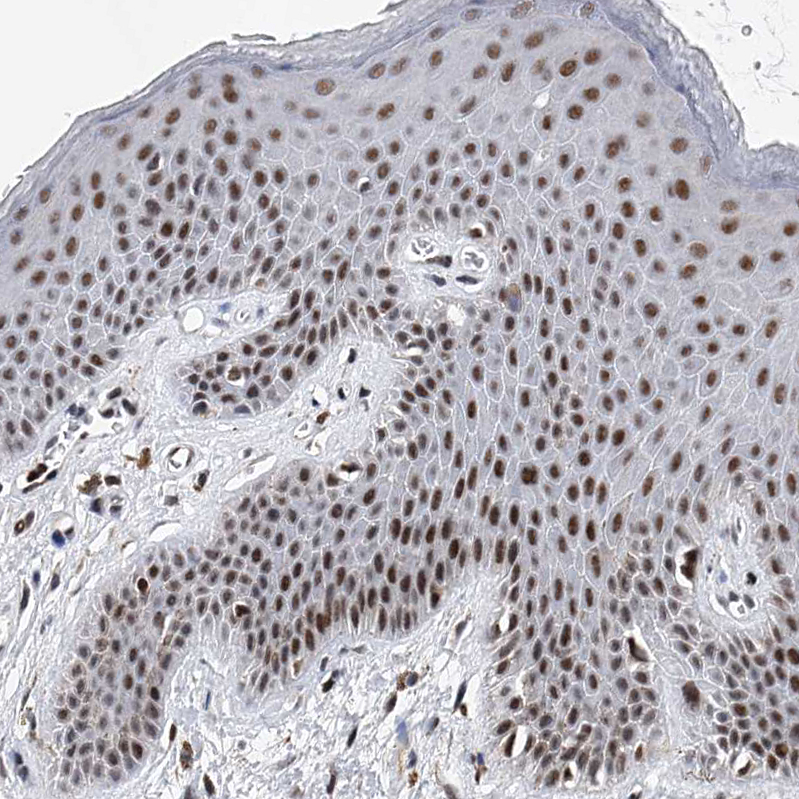

Immunohistochemical staining of human skin shows moderate to strong nuclear positivity in squamous epithelial cells.